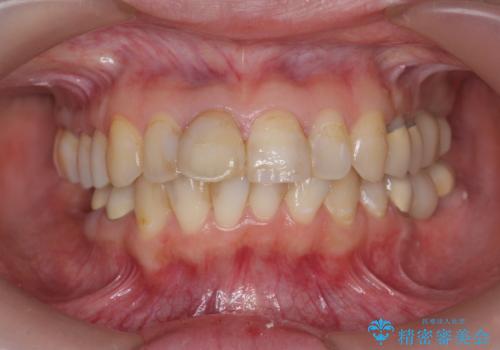

- 20代女性

- 「地元の歯医者にずっと通っているが、どんどん歯が悪くなる。時間とお金がかかってもいいので徹底的に歯を治したい。」

、と総合的な歯科治療を希望されて来院されました。

虫歯や咬合関係・歯槽骨の吸収・根尖病変・歯の欠損・複合的な問題を一つずつ解決し、

安定した噛み合わせの構築・歯ブラシのしやすい環境の整備・歯内歯周の感染除去・造骨を伴うインプラント治療

を行い、長期的な予後を見込める口腔内環境を確立、整備して行きます。